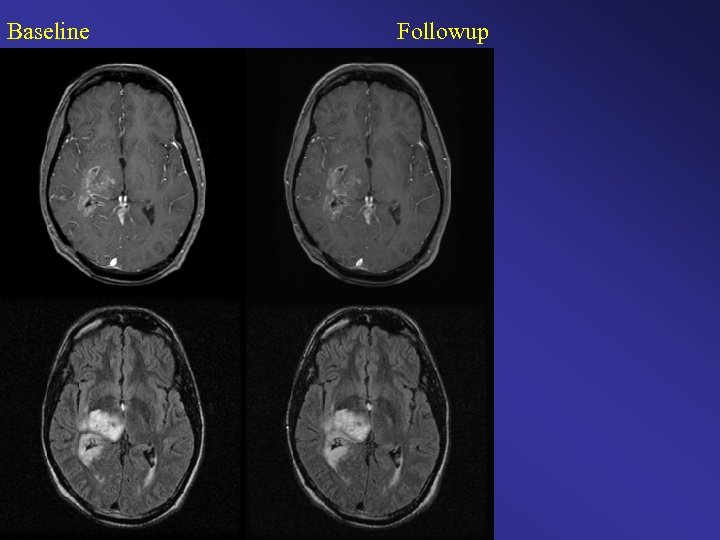

Baseline Followup

Baseline Followup Color Change Map Original Clinical Interpretation: Stable / Time to Progression Diagnosis = 7 months